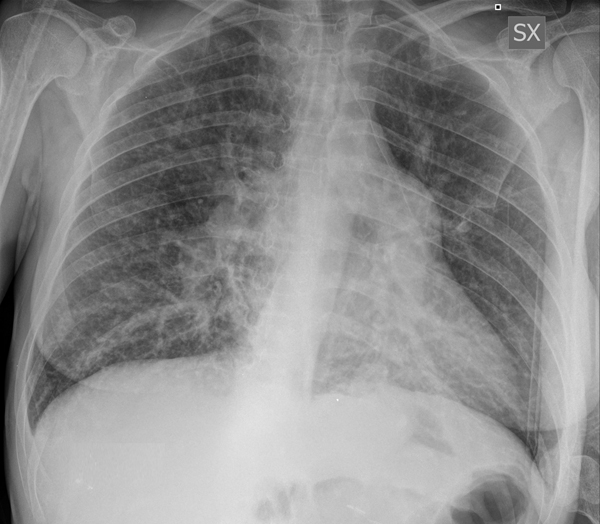

Chest X-ray (Figure 1) and chest CT (Figure 2), compared with the previous tests available, showed an unchanged picture of bilateral bronchiolitis characterized by millimetric center-lobular nodulations partly confluent and by thickening areas located in the medial segment of the middle lobe, in the lingula and in the postero-basal regions of both lower lobes, with greater extension to the left. Instead, a small, faint left retrocardiac thickening had appeared. Therefore, at ward admission, the patient was diagnosed with lower respiratory tract infection, with partial respiratory failure, in a CVID picture.

Figure 1. Chest X-ray performed in August 2021.

SX = left